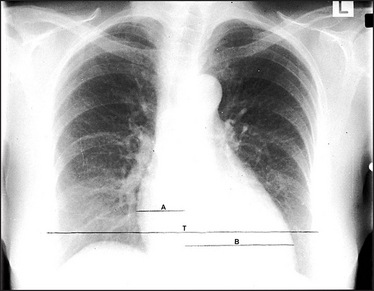

Figure 8.3 Pulmonary venous congestion The heart is enlarged due to failure. This failure is not severe enough to cause pulmonary oedema. However, the increased pulmonary venous pressure has caused upper zone blood diversion so that the vessels above the hilum appear wider than those below. (The mechanism of the blood diversion is not fully understood.) These changes are seen when the pulmonary venous pressure is about 15 to 20 mmHg. The cardiothoracic ratio A + B is a useful indicator of cardiac enlargement if it is greater than 50%. The thoracic measurement (T) is the widest diameter above the costophrenic angles, usually at the level of the right hemidiaphragm. The cardiac diameter is the addition of the two widths A and B.